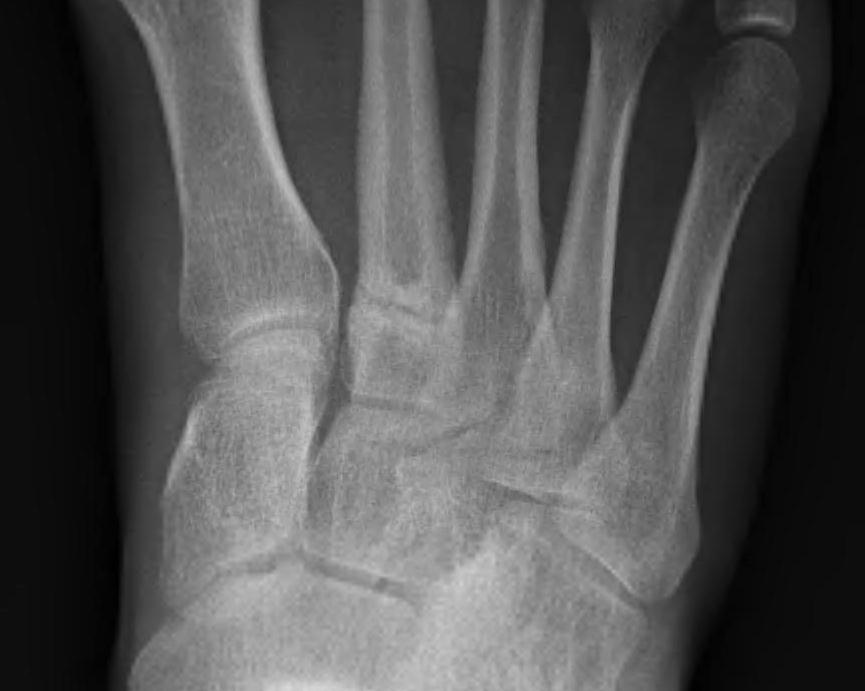

X-ray

May be negative for first 2 - 4 weeks

Subtle transverse / oblique fracture

- usually midshaft or distal

- usually incomplete

May see callous